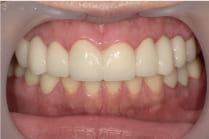

【27歳女性の症例】

「虫歯が気になっていたけど、忙しくてなかなか治療に行けなかった…」

そんな不安を抱えてご来院された27歳の女性。

上下合わせて16本の虫歯治療を行いました。

1回目の治療時に虫歯を取って、根の治療を行ったのち、仮歯をいれました。

このような状態でもすぐに見た目が気にならなくなりました。

その後根の治療をし、土台をいれてから口腔内スキャナーでスキャンしました。

スキャンデータを用いて、ジルコニアセラミックを作成し歯にかぶせて治療終了です。

治療回数は7回でした。

術後は見た目だけでなく、噛み合わせや口腔内の健康も大きく改善されました。

歯の悩みは、放置せずに一歩踏み出すことが大切です。

私たちは、どんな状態からでも丁寧にサポートします。

治療をすればこの様にきれいになります。